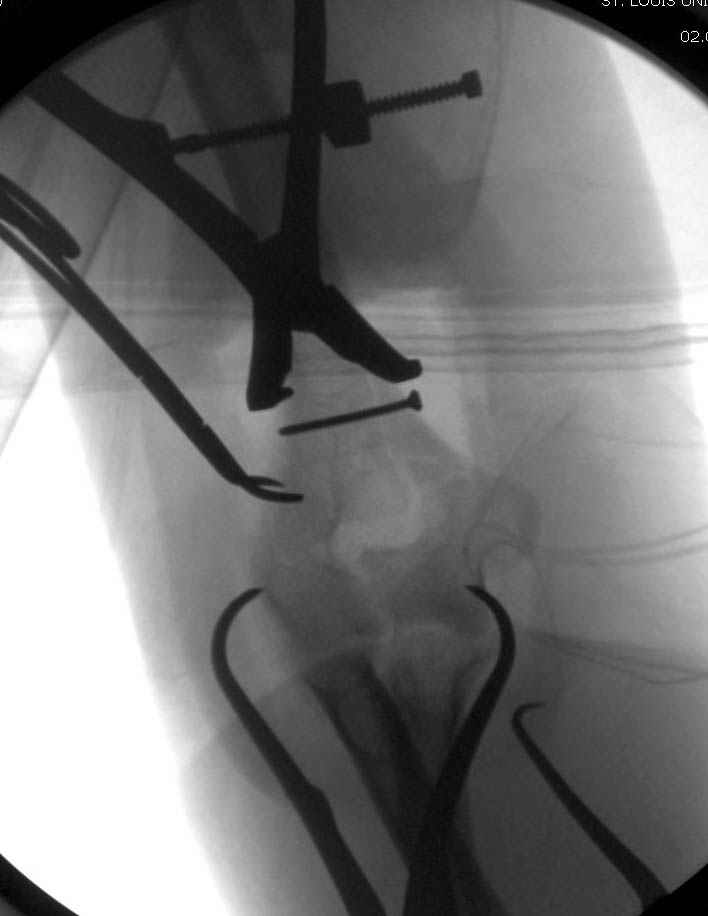

Djoldas Kuldjanov, M.D. 09 Сентябрь 2005, 20:07

Примерный случай, только перелом был открытый, в задне-медиальной стороне рана около 2 см по характеру "изнутри кнаружи", неврологический статус со слабостью сгибания мизинца, также слабая абдукция и аддукция указательного пальца и сгибания в кисти.

Больному сделали обработку и наложили временный аппарат внешной фиксации плечо-предплечье.

На шестой день сделали открытую репозицию чрезлоктевым доступом двумя locking plate, локтевой нерв был ушибленным, после операции положительная динамика в Flexor Carpi Ulnaris. Фиксацию локтевого отростка произвели tension band technique с дополнительным шурупом.

Этапы операции на снимках....

Джолдас Кульджанов

Djoldas Kuldjanov, MD

Department of Orthopedic Surgery

St. Louis University Medical Center